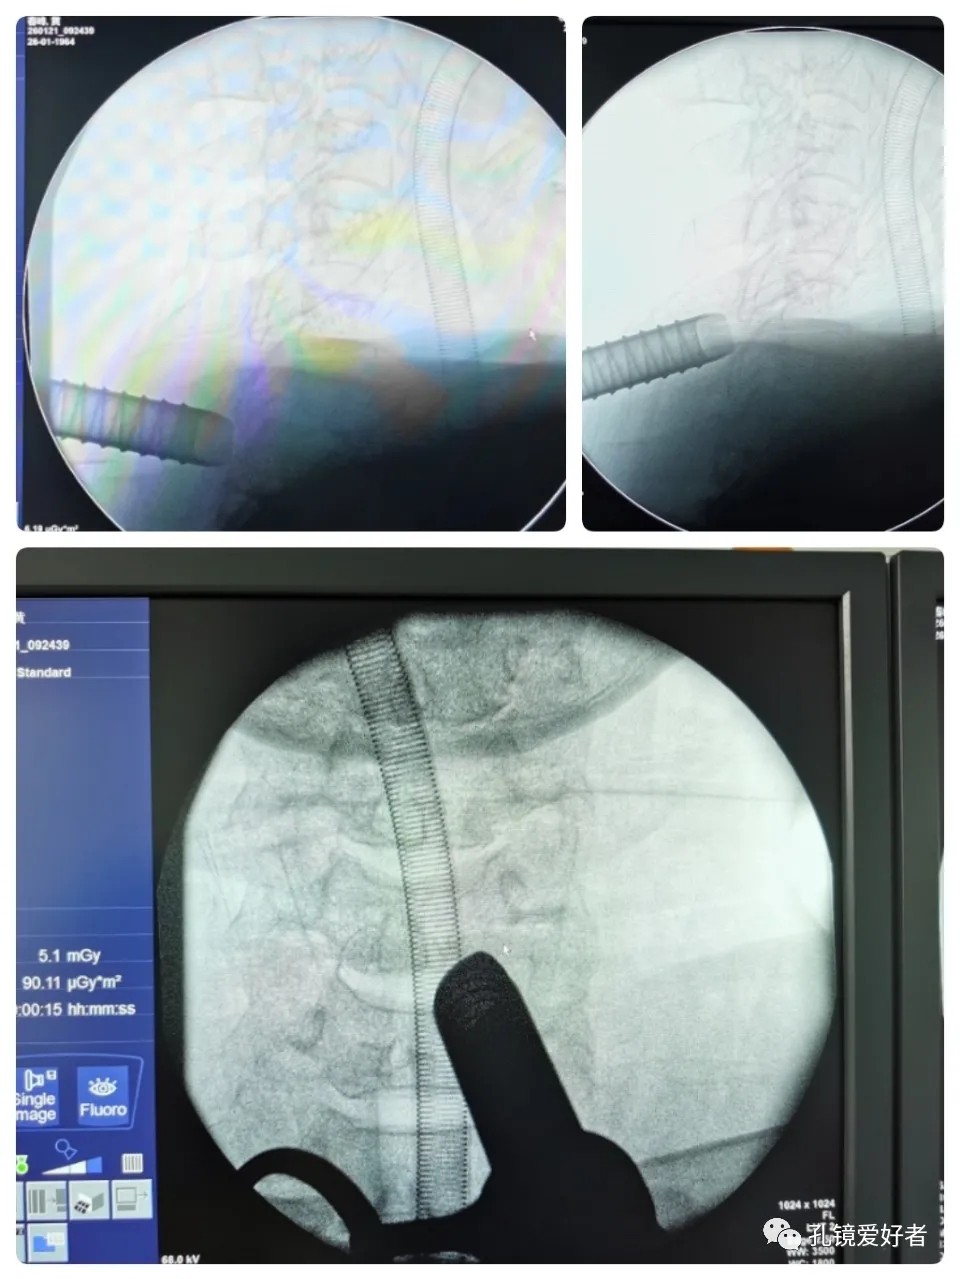

Syringe Needle For Positioning

A soft tissue expansion tube was placed through the incision.

The threaded tool specially designed for using the Delta system were well placed.

A vessel clamp was used for stabling the tool so that it could lead to the right segments through the portal.

C-arm X-ray

From the AP side, it can be seen that the surgical tool is well placed next to the spinous process, which is not far away. From the lateral side, it can be seen that by moving the surgical tool up and down, it can cross the entire lamina of C6 to reach both the upper and lower spaces of the vertebrae.